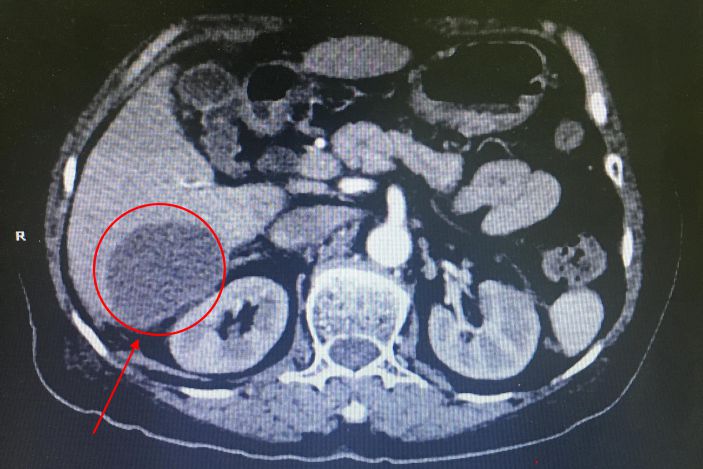

許婆婆,74歲,流沙人,反複上腹部疼痛,伴有發熱1個月。在外院就診,但一直得不到很好的診治。病情反複,高熱39℃,日漸消瘦。3月25日轉至我院就診,收住外一科。

△術前病竈部位

經CT檢查發現患者肝右葉S5、S6、S7段多發膿腫,病竈最大的達6.0*4.2cm,結腸肝曲周圍炎性滲出。據了解,肝膿腫是肝髒化膿性病變,若不積極治療,死亡率達10%-30%。